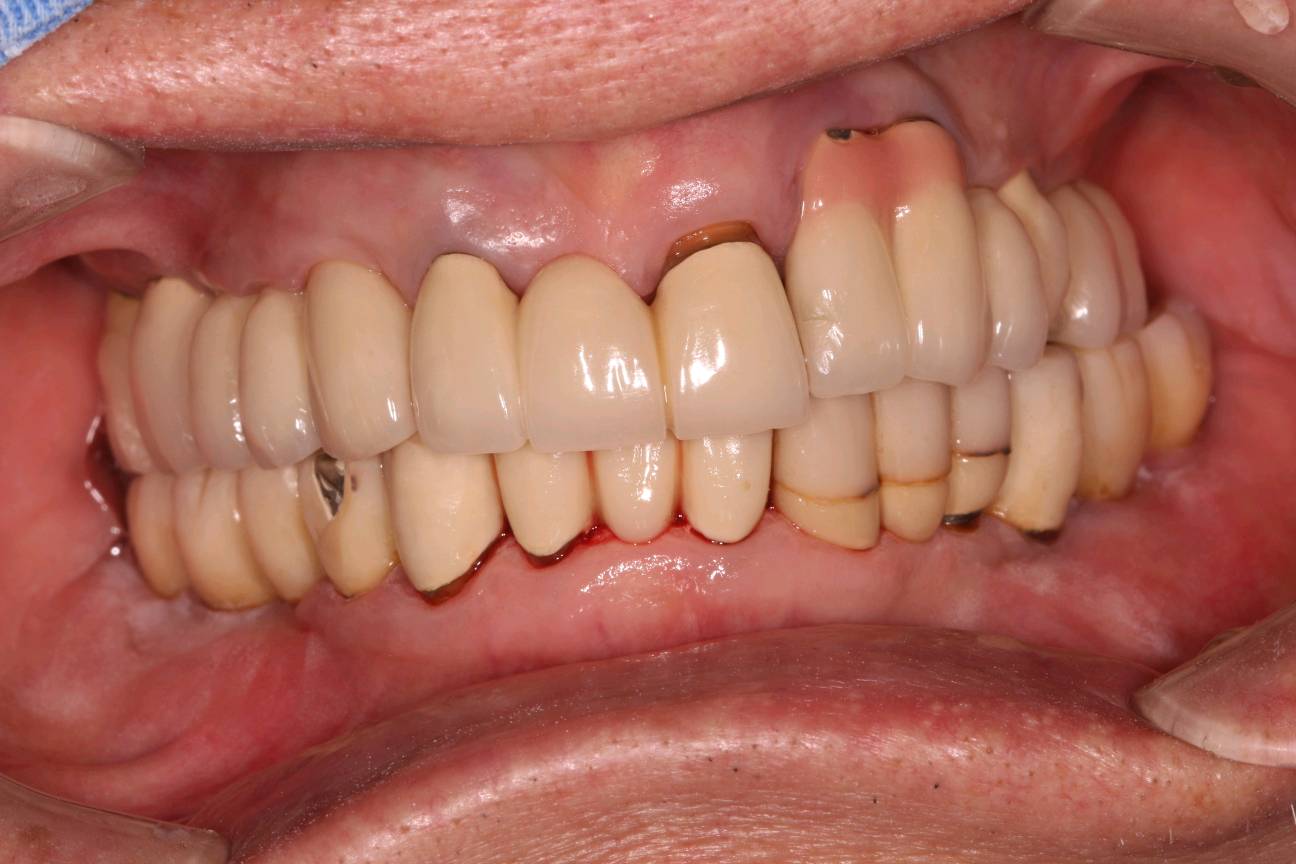

程先生,80岁种植牙复诊,共种了17颗牙,距离第一颗种植牙己定期随访15年,无松动疼痛等症状,用的很是满意。

本次复诊进行了OHI口腔卫生宣教,刷牙、牙线、间隙刷使用宣教和全口超声波洁治,喷砂洁治,抛光,上药,并愉快的约了明年今日复诊。